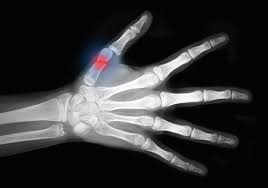

A continuación enumeramos los signos y síntomas de un trauma en los huesos

1. Dolor

Es el síntoma más frecuente y constante; en la práctica clínica no hay fracturas indoloras.

Se manifiesta como un dolor generalizado a una extensa zona, pero es muy preciso, localizado y extremadamente intenso en el sitio mismo de la fractura (one finger pain); allí es perdurable en el tiempo y puede ser muy relevante para indicar la existencia de una fractura.